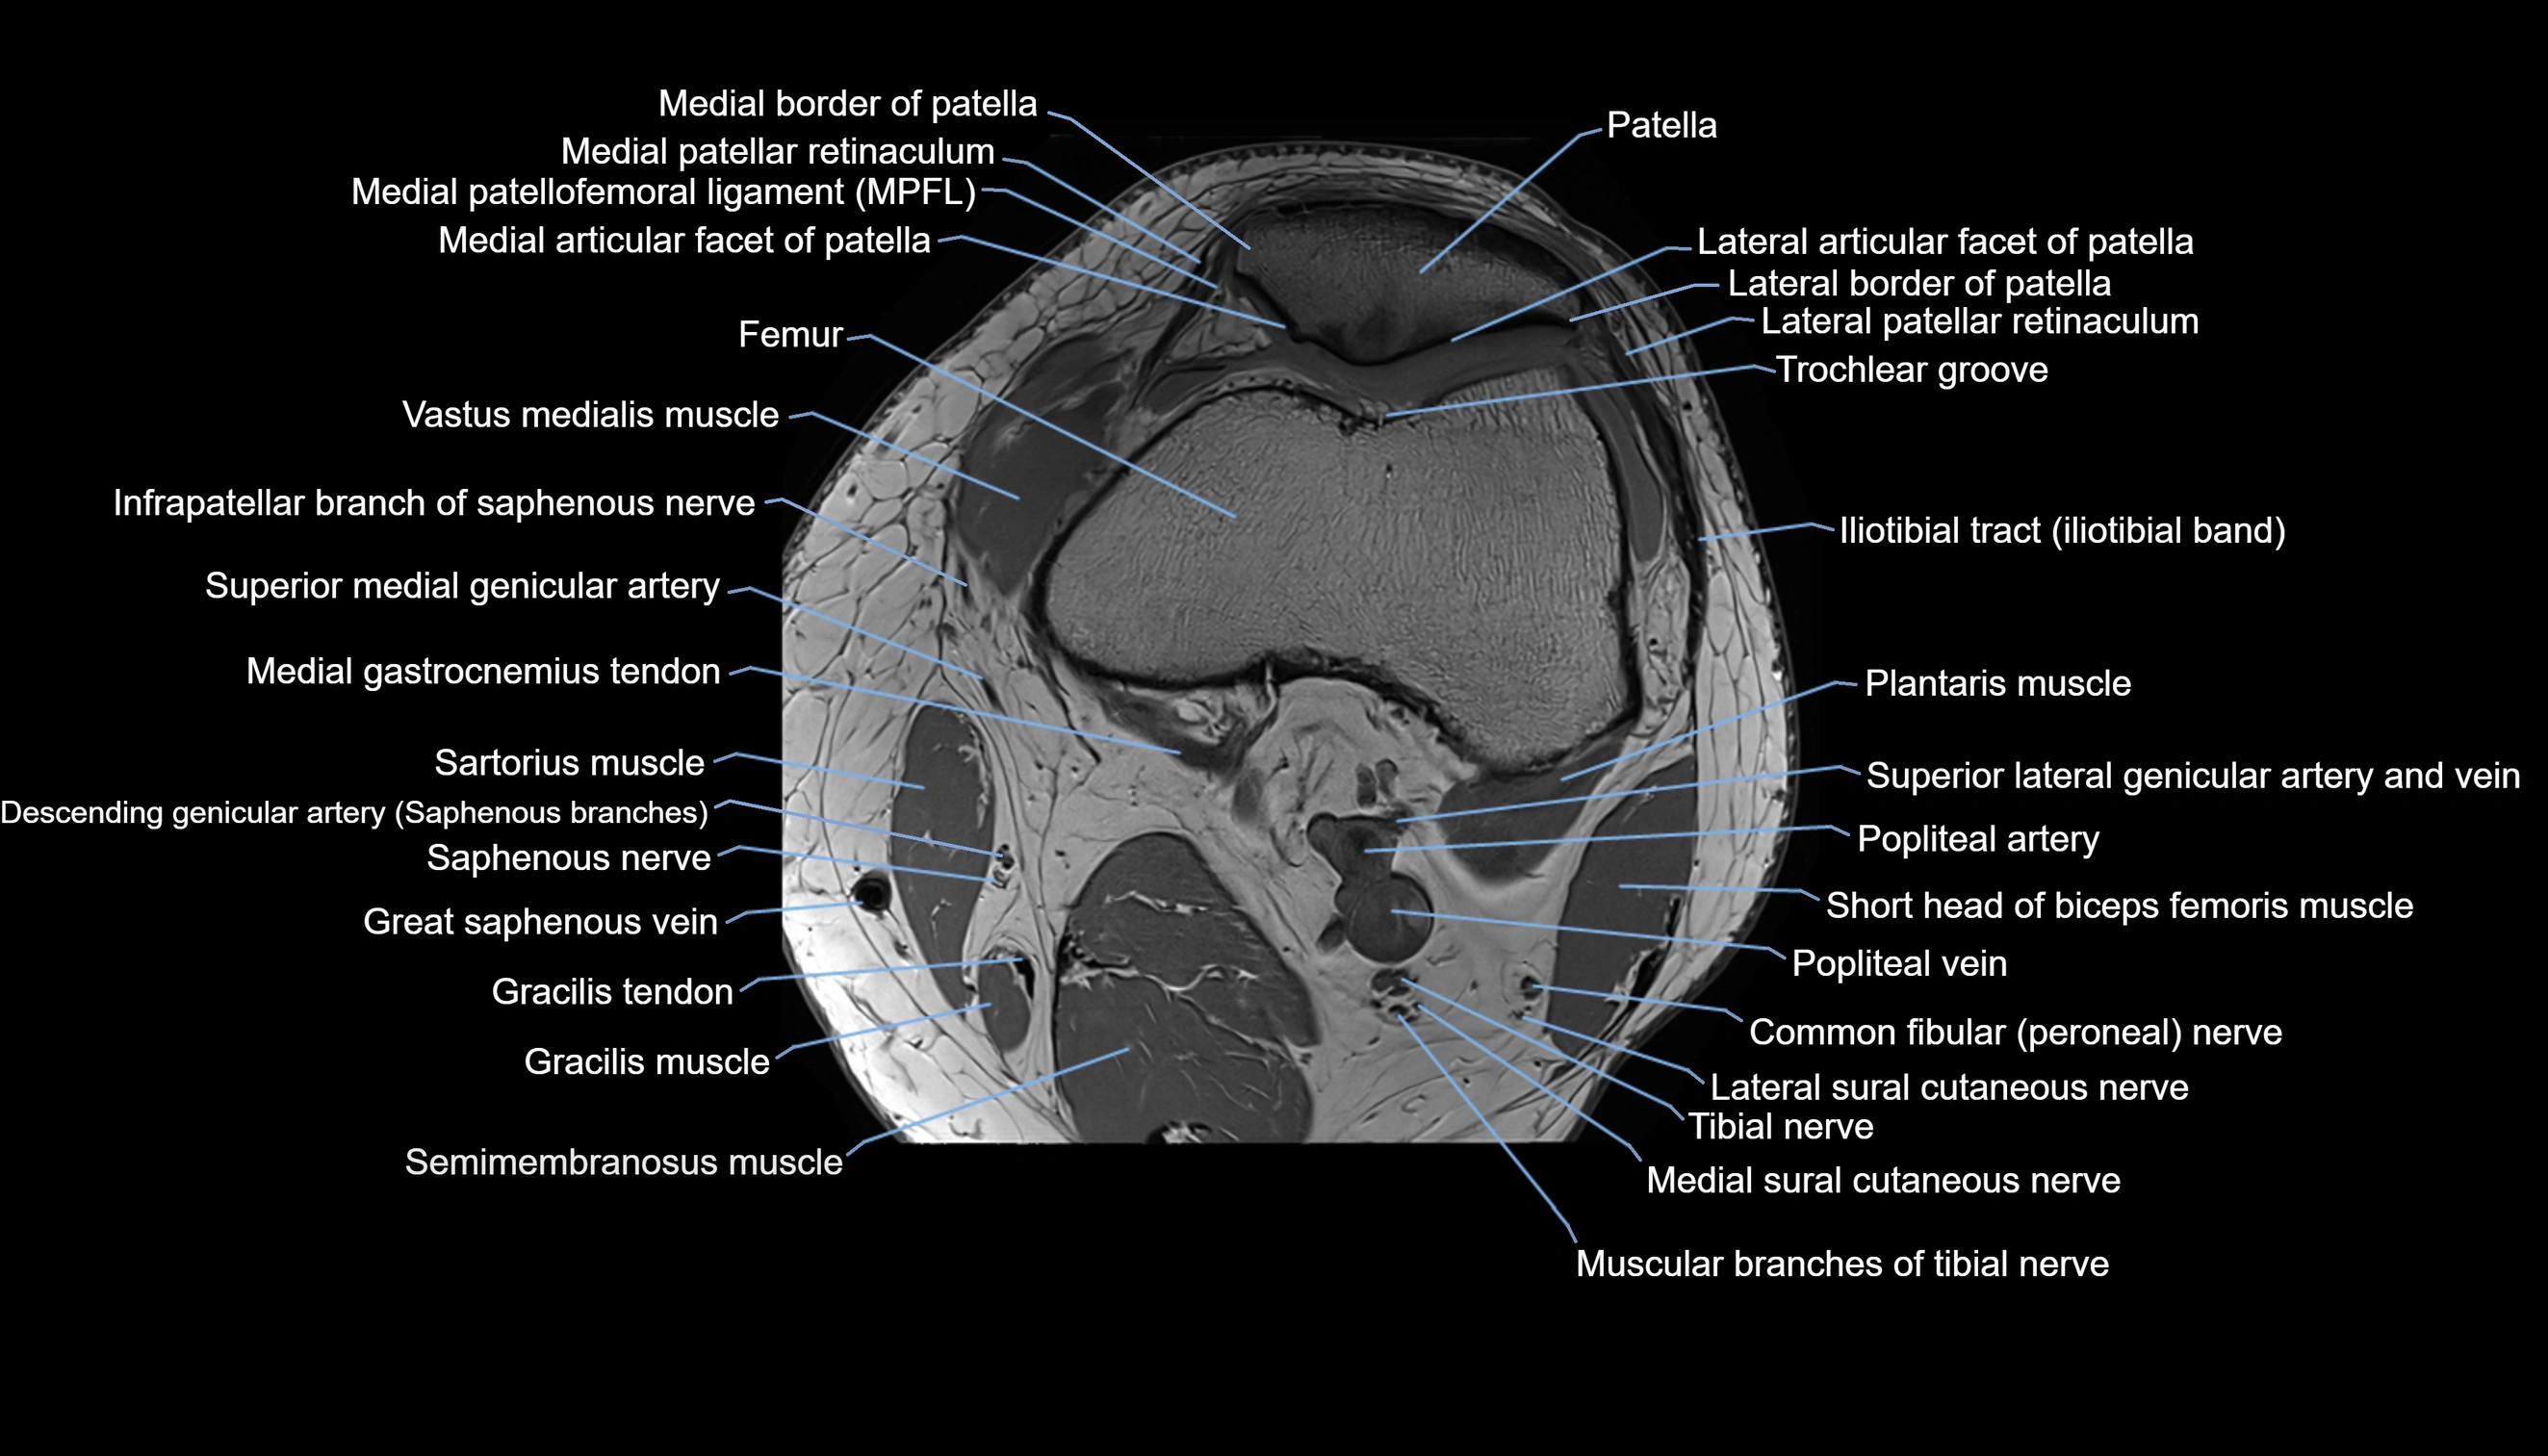

- Infrapatellar branch of saphenous nerve

- Lateral articular facet of patella

- Lateral border of patella

- Lateral patellar retinaculum

- Lateral patellofemoral ligament

- Medial articular facet of patella

- Medial border of patella

- Medial gastrocnemius tendon

- Medial head of gastrocnemius muscle

- Medial patellar retinaculum

- Medial patellofemoral ligament

- Medial sural cutaneous nerve

- Muscular branches of tibial nerve

- Patella

- Popliteal artery

- Popliteal vein

- Sartorius muscle

- Semimembranosus muscle

- Superior lateral genicular artery

- Superior lateral genicular vein

- Superior medial genicular artery

- Tibial nerve

- Trochlear groove

- Vastus medialis muscle

- great saphenous vein